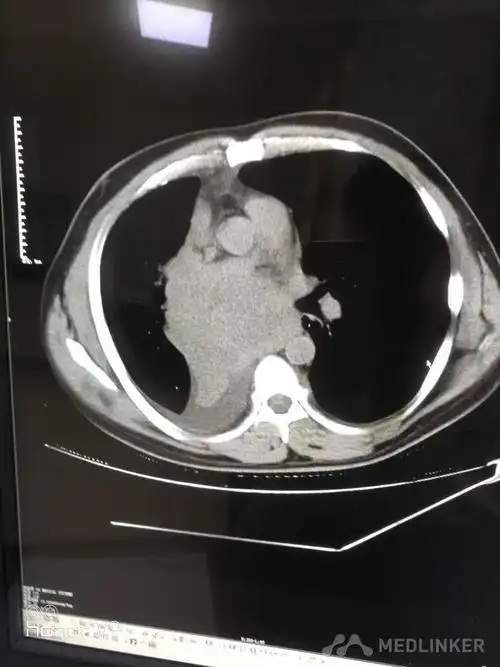

中央型肺癌ct

简述中央型肺癌特点及影像表现

在ct上,肺癌按照发生部位可以分为以下3种类型: 1,中央型肺癌:指肿瘤

影像基础知识:中央型肺癌ct表现及报告书写!

中央型肺癌一例直接征象和间接征象都有哪些